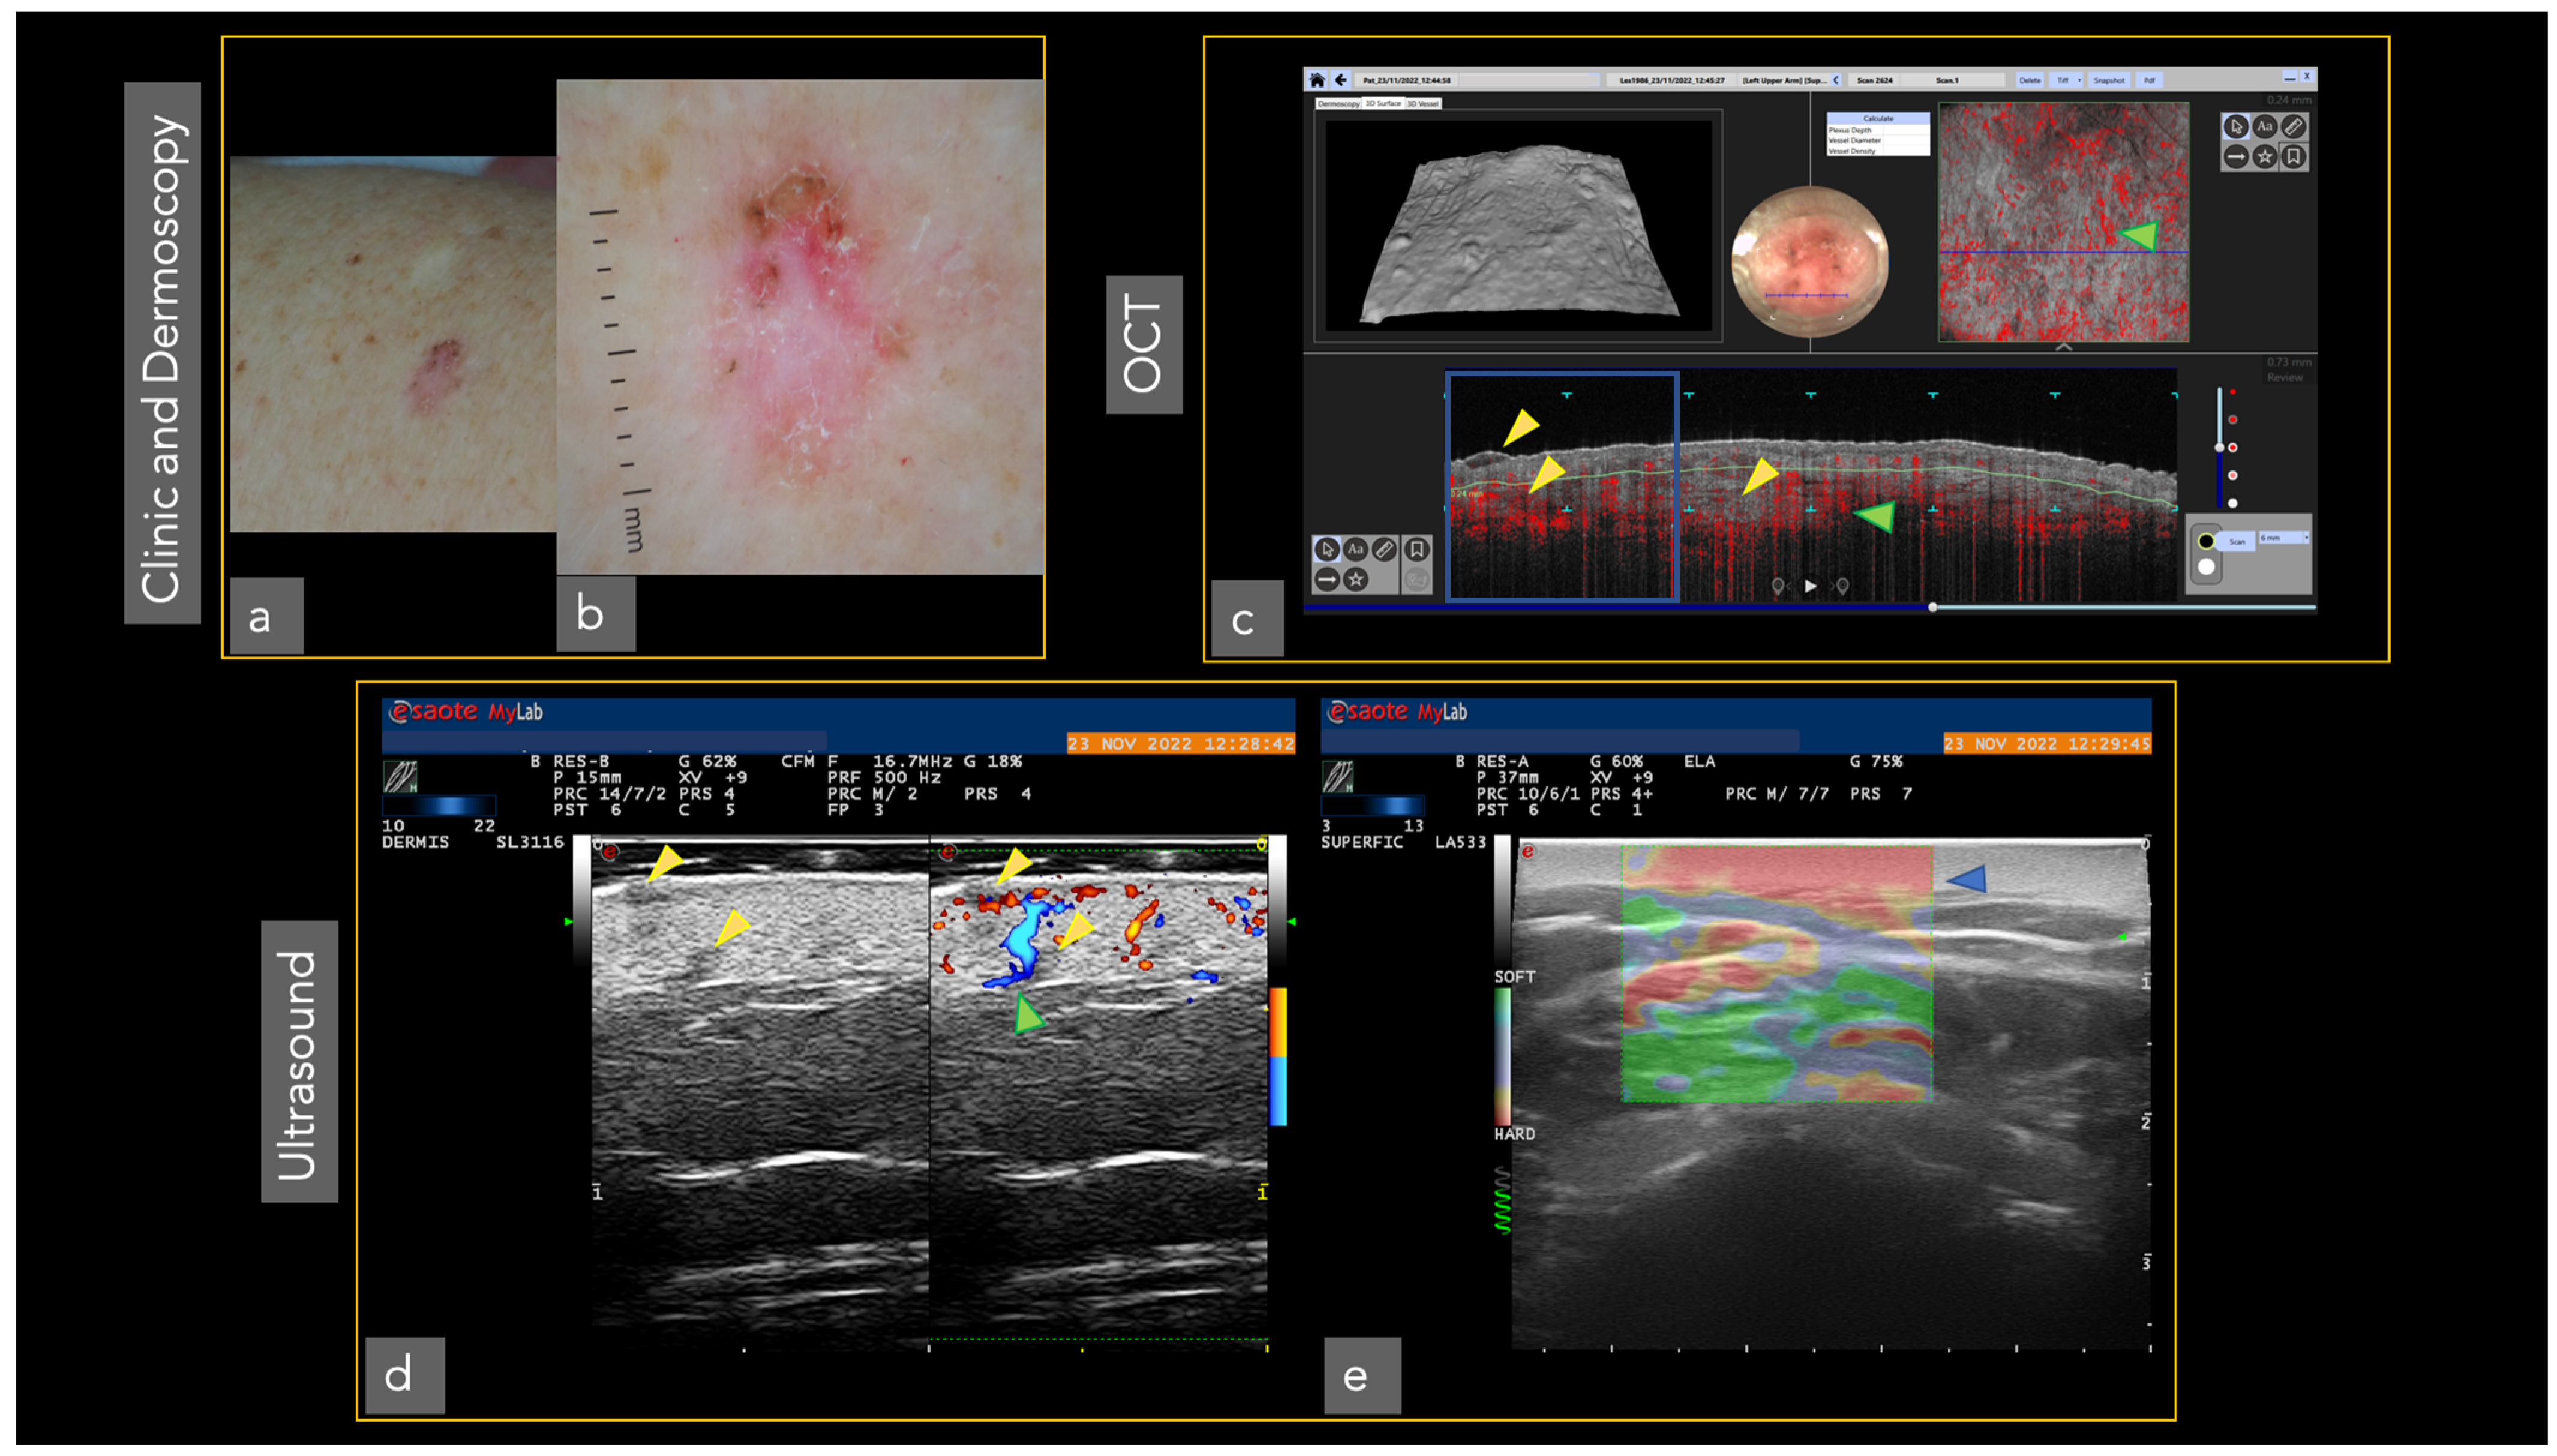

Different imaging techniques are represented in Figure 1 and Figure 2, in which the same superficial and infiltrating basal cell carcinoma has been studied with different in vivo techniques.

Figure 1.

Superficial and infiltrating basal cell carcinoma in the left arm was studied with different techniques. Tumor presence (yellow triangles). The vascular pattern is represented with green triangles: (a) Clinical image; (b) Dermoscopy; (c) OCT showing superficial and infiltrating basal cell carcinoma (blue square). The tumor surface is perceived (superior left). Dermoscopy area scanned (center). The vascular pattern can also be observed in 3 D (superior right); (d) The same tumoral islands are observed in ultrasound (left). The addition of the Doppler image reveals the complete tumor invasion (right); (e) The elastography shows the denser area corresponding to the tumor (blue triangle). Ultrasound image courtesy of Dr. Priscila Giavedoni.